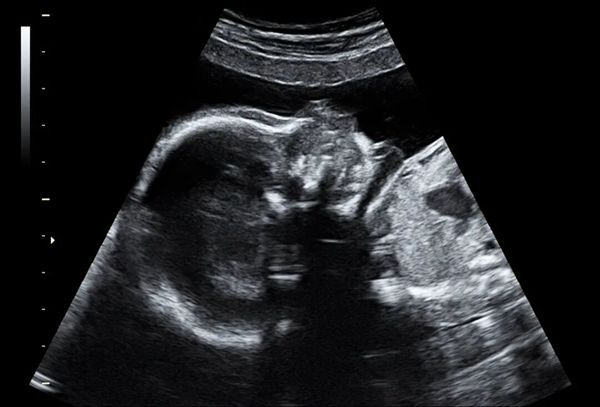

2025年春天,她终于第一次听到了胎心。

那一声有力的搏动,像是生命对她说:“你辛苦了,这次我不走了。”